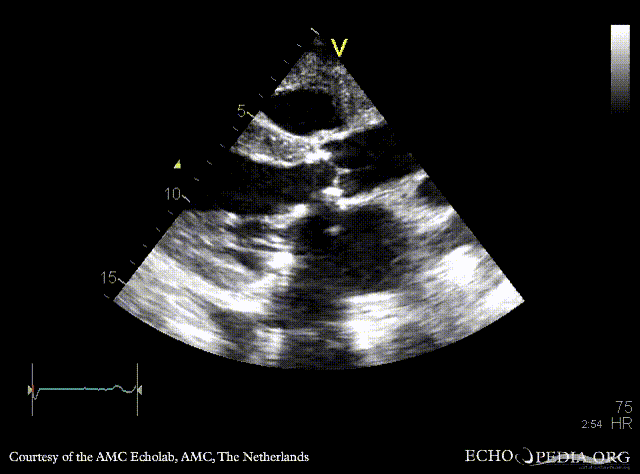

PSAX: aortic bioprosthesis